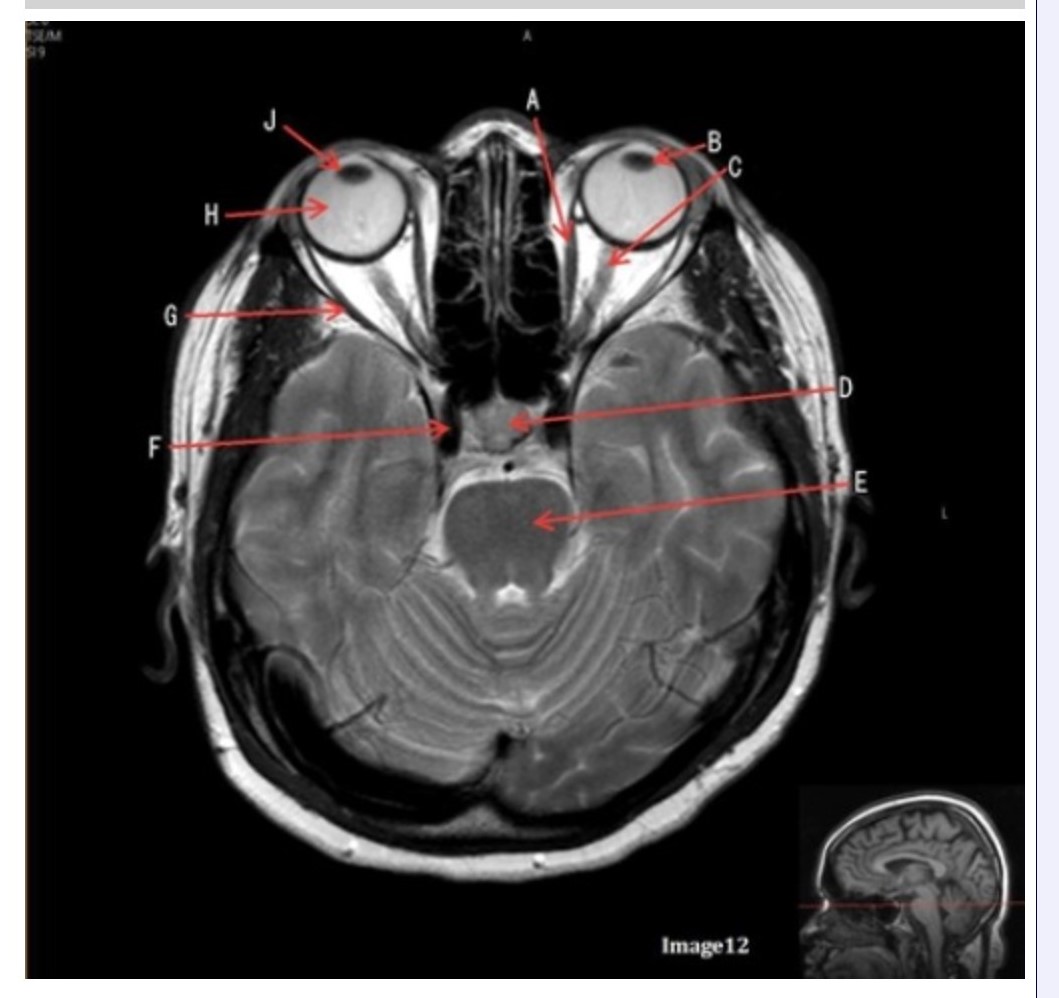

Letter H in Image 12 is pointing to:

A. Lens

B. Lateral rectus muscle

C. Medial rectus muscle

D. Internal carotid artery

E. Globe

Letter B in Image 12 is pointing to:

A. Left optic nerve

B. Lateral rectus muscle

C. Medial rectus muscle

D. Lens

E. Midbrain

Letter J in Image 12 is pointing to:

A. Globe

B. Lateral rectus muscle

C. Medial rectus muscle

D. Right lens

E. Left lens

Letter F in Image 12 is pointing to:

A. Lens

B. Lateral rectus muscle

C. Medial rectus muscle

D. Internal carotid artery

E. Globe

Letter C in Image 12 is pointing to:

A. Left optic nerve

B. Lateral rectus muscle

C. Medial rectus muscle

D. Lens

E. Midbrain

Letter D in Image 12 is pointing to:

A. Optic nerve

B. Pituitary gland

C. Globe

D. Lens

E. Midbrain

Letter G in Image 12 is pointing to:

A. Lens

B. Lateral rectus muscle

C. Medial rectus muscle

D. Internal carotid artery

E. Globe

Letter E in Image 12 is pointing to:

A. Optic nerve

B. Pituitary gland

C. Globe

D. Pons

E. Left lens